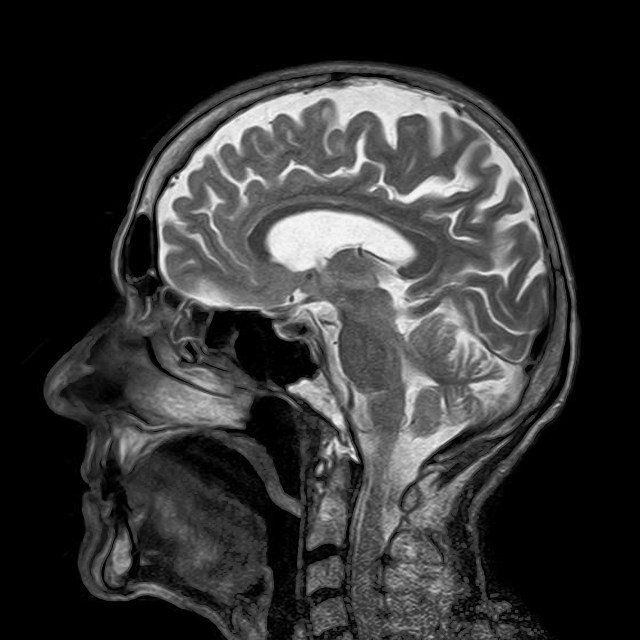

India, like Canada and the United Kingdom, defines brain death as “brain stem death.” The brain stem standard defines legal death as “irreversible loss of the capacity for consciousness combined with the irreversible loss of the capacity to breathe.” Key components of consciousness and respiratory control are found in the brain stem, and their loss results in brain stem death. Preserved cortical electrical activity and intracranial blood flow are compatible with brain stem death.

The United States and much of Europe use the whole brain death standard for determining death. Whole brain death is the “irreversible cessation of all functions of the entire brain, including the brain stem.” Even with whole brain death, however, islands of functioning brain tissue, as well as electrical and hormonal brain activity can persist. By either definition brain death is irreversible.

The Reanima Project aims to change this. But, will the modest outcomes of the proposed study match the immodest claims of “curing” brain death and restoring consciousness? The primary outcome measure of the study is “reversal of brain death as noted in clinical examination or EEG.” However, electrical activity as recorded by EEG is compatible with brain death of either kind. A claim to have reversed brain death cannot be based on evidence of something that is already present in brain death. Secondary outcome measures include brain imaging to detect neurogenesis; and pulse, oxygen saturation, blood pressure, and respiration changes. Of these, only respiration changes would indicate recovery from brain death, and then only if spontaneous breathing was restored.